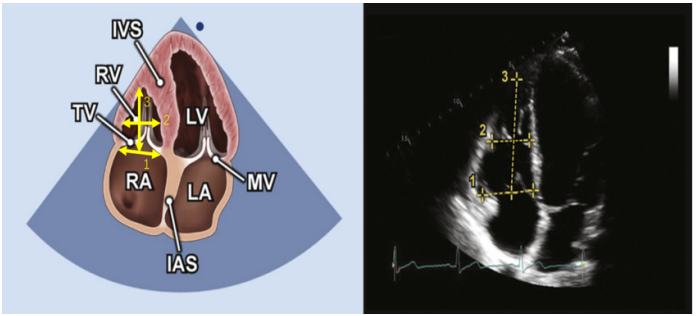

其次,观察心腔的大小。此处根据重症超声评估血流动力学的思维,先从右心评估开始。常规首选心尖四腔心切面(A4C)进行相关测量,在该切面可以测量右心室的上下径和左右径。该方法测量的三尖瓣瓣径通常小于2.8 cm,超过3.9 cm即为重度扩张。中间段直径参考值小于3.5 cm,超过4.2 cm为重度扩张。上下径小于7.9 cm,超过9.2 cm为重度扩张。操作示意图见图2。

图片

图2. 心尖四腔心切面A4C下测量右心室上下径(线段3)和瓣环径(线段1)和中间段内径(线段2)的示意图